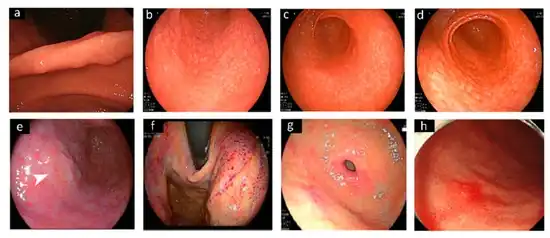

-

Different endoscopic patterns related to H. pylori infection.[106] -